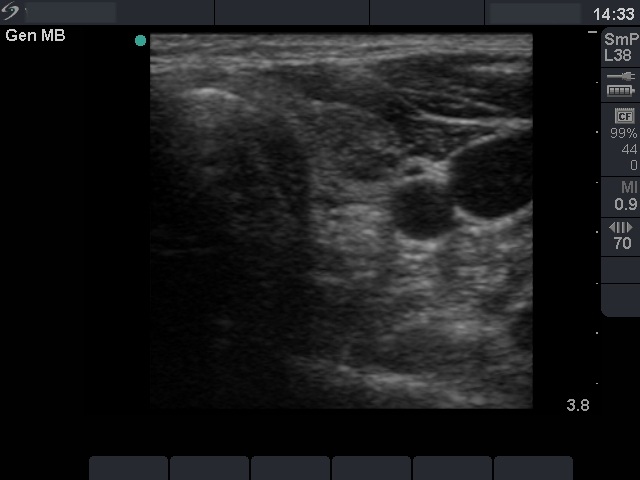

Oxyphilic adenoma - Case 19. (ultrasonographic picture 4)

Left lobe, horizontal scan. A hypoechogenic inhomogeneous nodule in the lobe. It contains microcalcifications.